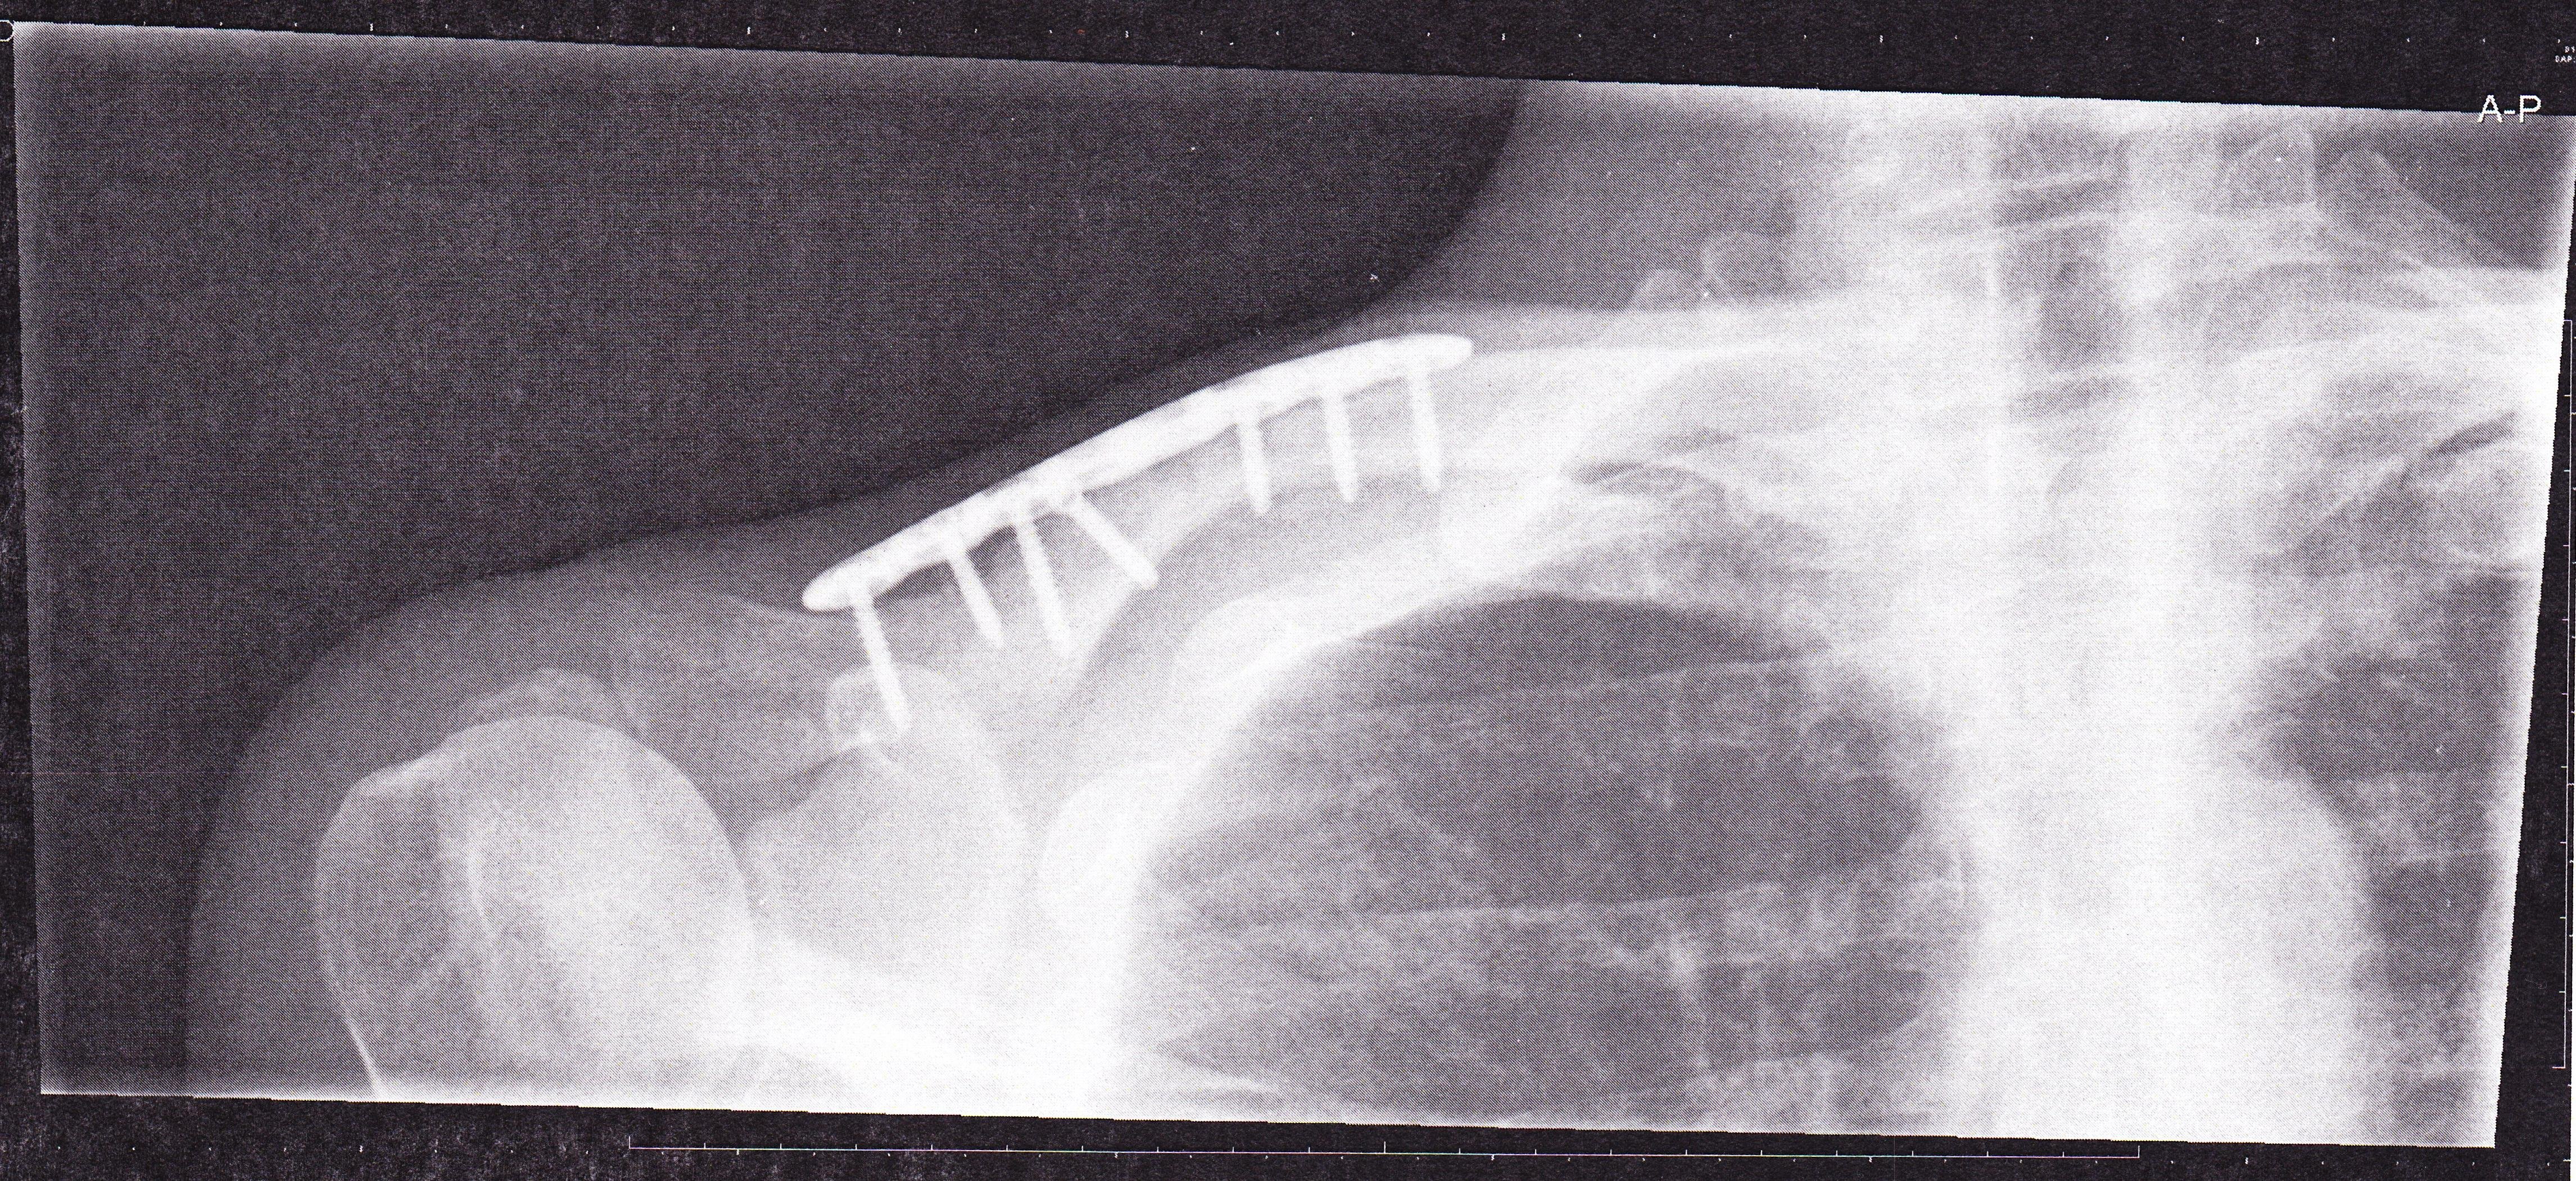

En nu zit ik hier mee, een titanium plaat en schroeven op mijn schouder. Ik fietste naar huis en een auto uit tegengestelde richting wilde linksaf slaan op het moment dat ik bij de afslag was. Moest vol in de remmen om niet aangereden te worden, vloog over het voorwiel en knalde met mijn schouder op het wegdek. Hij had me volledig over het hoofd gezien.

Afbeelding

Maar waarom lijken die schroeven er helemaal doorheen te gaan?

dat de schroeven iets doorsteken, komt meer voor. rond het bot zit voldoende 'vlees' om dit geen probleem te laten zijn. je hebt eerder last van de plaat. mogelijk kan die er na een tijdje (jaar) af/uit.

Ik moet 9 feb voor controle en dan ga ik dat ook aankaarten. Botten zijn van nature immers iets flexibel en met zo'n plaat is dat weg. Als het kan wil ik dat ding er op termijn wel uit hebben.

Het lijkt me niet meer dan logisch dat dit op termijn verwijdert wordt.